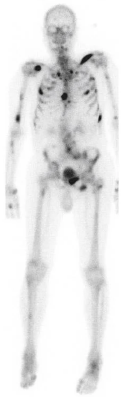

Métastases

La propagation des cellules cancéreuses est un phénomène possible pour den ombreux cancers. En effet, certaines cellules cancéreuses peuvent quitter la tumeur principale, voyager dans le sang ou la lymphe, et s’installer dans d’autres organes. Elles y forment de nouvelles tumeurs appelées métastases